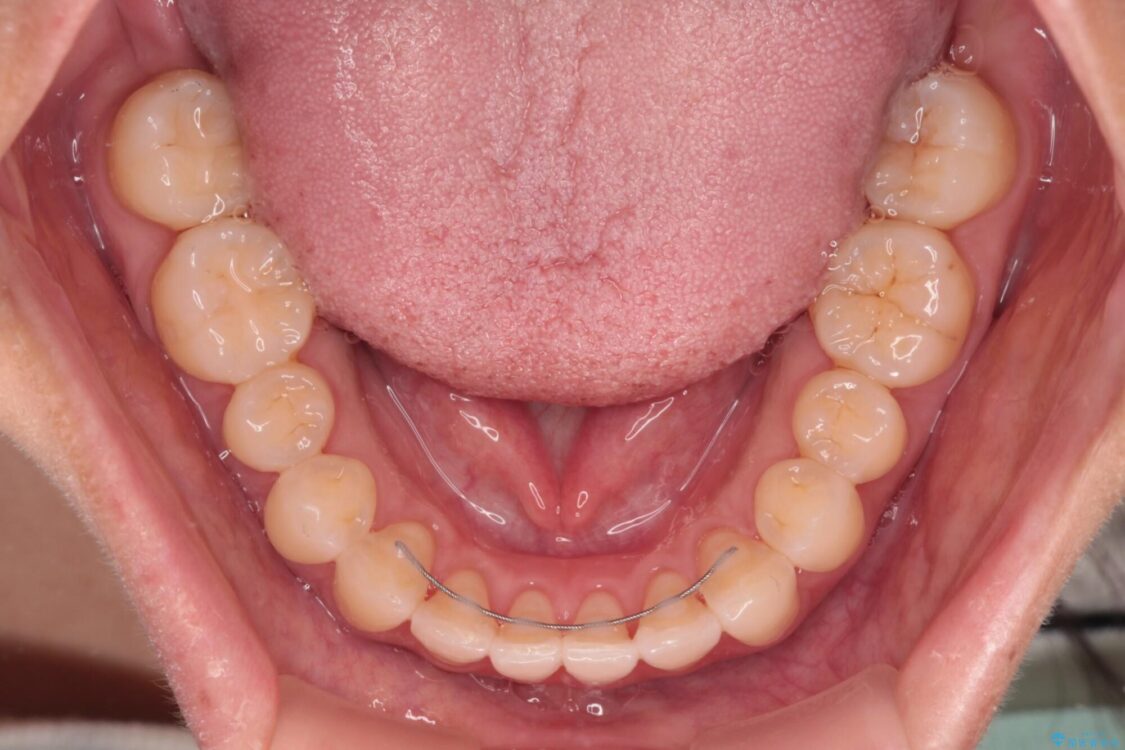

治療後

• 【モニター】前歯のデコボコをインビザラインで改善 治療後画像